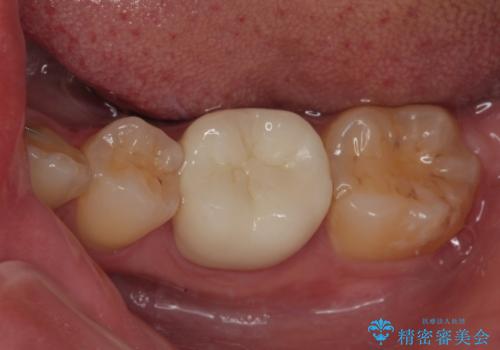

左下にフロスを通すと引っかかる オールセラミッククラウン

担当医 有澤哲郎